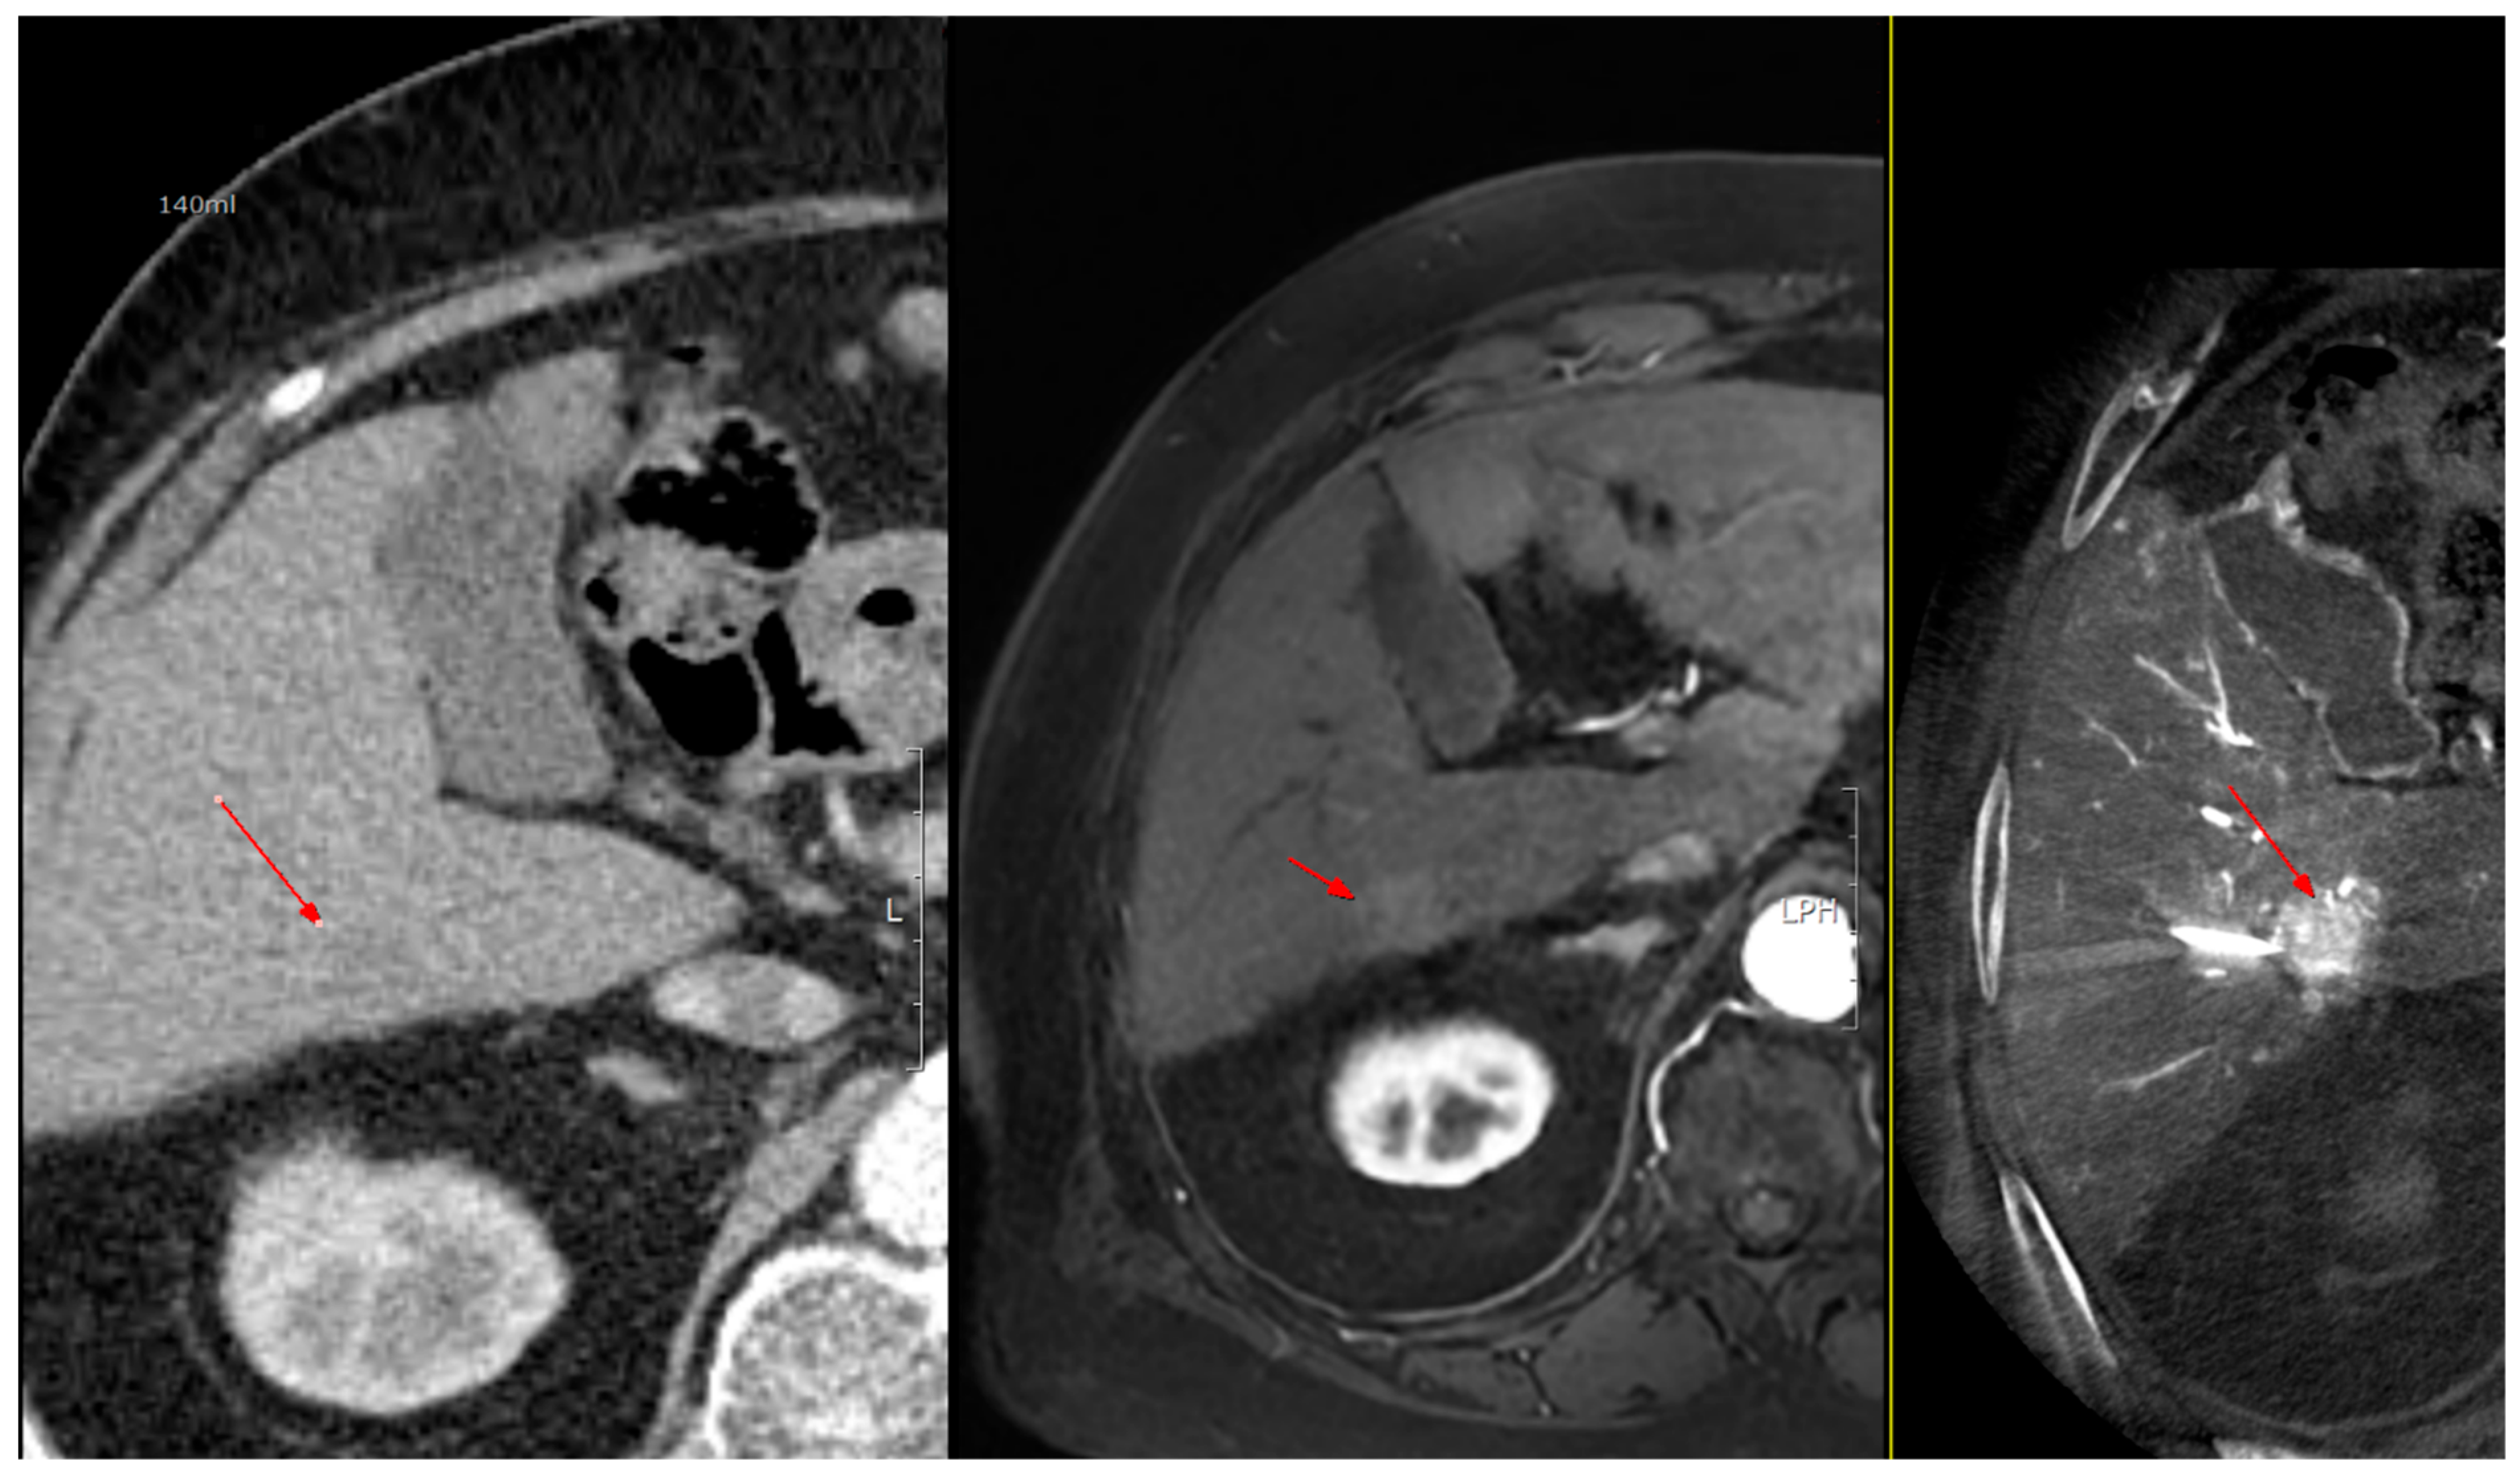

As shown in Figure 1, angio-CBCT allows for higher visibility of the target mass, as reflected in the ΔHU values. This can be visually confirmed in several cases. Representative cases in Figure 2 and Figure 3 demonstrate how the target mass is much more conspicuous to the operator on angio-CBCT compared to pre-procedural CT. In Figure 4, a mass, which was nearly invisible on pre-procedural CT, was identified through angio-CBCT, aiding the targeting process. Figure 5 shows a case where a mass with discordance between USG and CEUS was confirmed using angio-CBCT, leading to needle repositioning and achieving complete ablation. Finally, Figure 6 illustrates a case where a residual tumor was identified on angio-CBCT and re-ablation resulted in complete ablation.

Figure 2. CT images from a patient with hepatocellular carcinoma undergoing angio CBCT-guided RFA. (Top): pre-procedural CT (portal venous phase; lesion 128.7 HU, red arrow = HCC mass). (Bottom): intraprocedural angio CBCT (lesion 1499.7 HU, red arrow with star = HCC mass). ΔHU = 1298.0 HU. (intra lesion − intra background) − (pre lesion − pre background).

Diagnostics 15 02898 g002